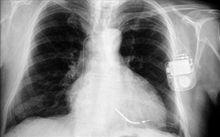

胸部X線表現:①孤立性肺囊腫。液囊腫為圓形或橢圓形,密度均勻,邊緣光滑的陰影。氣囊腫為薄壁環形陰影。張力性含氣囊腫可形成巨大的氣囊,壓迫周圍肺組織,使縱隔向對側移位。液氣囊腫可見液平面,如囊腫內有間隔形成多房,可有多個液氣平面形成。合併感染時,囊壁增厚,囊腫周圍出現炎性浸潤性陰影。②多發性肺囊腫。肺野內見很多薄壁環形透光區,大小不等,相互重疊,似蜂窩狀。有時囊腔內也可出現液氣平面。